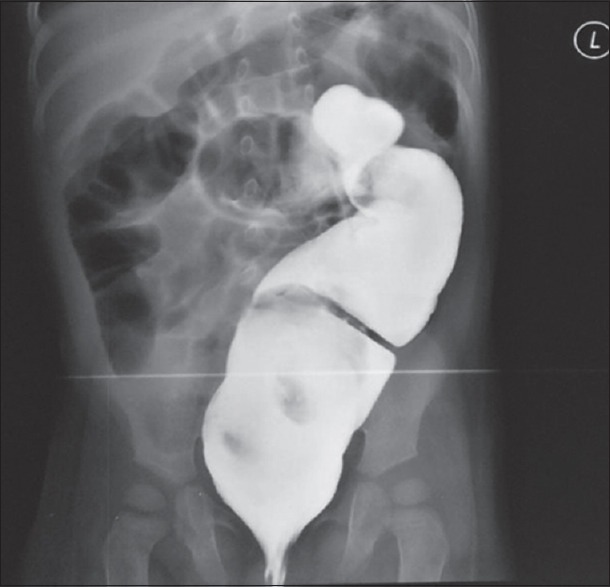

巨结肠病是儿科结直肠手术中较为常见的疾病。在过去的三十年中,治疗方式已经从第三阶段发展到单阶段。单阶段手术可以使用开放、经肛门或腹腔镜辅助技术进行。我们用这些病例来说明腹腔镜辅助手术治疗先天性巨结肠疾病在我中心的首例。腹腔镜辅助技术进行了描述,并讨论了机构间和机构内合作的经验教训。

Hirschsprung's disease is a relatively common disease in pediatric colorectal surgery. The treatment modalities have evolved from third-stage to single-stage in the past three decades. The single-stage procedure can be performed using the open, transanal or laparoscopy-assisted techniques. We use these cases to illustrate the first laparoscopically assisted procedures for Hirschsprung's disease in our center. The laparoscopic-assisted technique is described, and lessons in collaboration across institutions and within institutions are discussed.